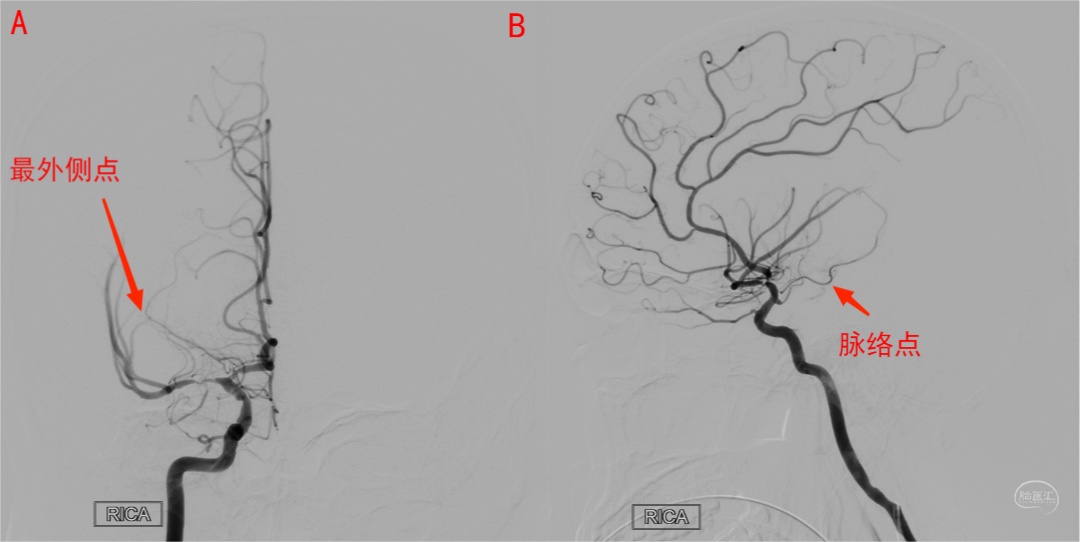

图12 右侧颈内动脉正位(A)及侧位(B)造影,由于大脑中动脉M1段狭窄,其对脉络膜前动脉的阻挡减少,从而使此例管径相对较粗的脉络膜前动脉显示更清晰。最外侧点易于在正位识别,脉络点易于在侧位识别。